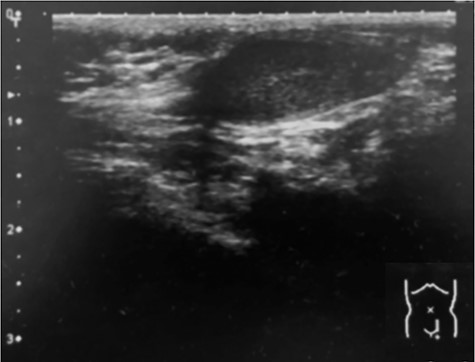

A14-month-old boy was admitted to our hospital to undergo inguinal orchidopexy. At the age of 1 month, the left testis was palpable between the inguinal canal and the scrotum. When he was 6 months old, ultrasonography showed the left testis inside the inguinal canal (Fig. 1). At the age of 13 months, the patient was seen in the outpatient clinic for preoperative examination in preparation for inguinal orchidopexy; the left testis was not palpable at that time. At the age of 14 months, we began surgery with a preoperative diagnosis of an undescended testis. When the inguinal canal was opened, only a patent processus vaginalis was visible (Fig. 2). After incision of the membrane, we were able to retrieve the testis from the abdominal cavity (Fig. 3a). The patent processus vaginalis was closed, a dartos pouch was created and the testis was guided into the pouch and fixed to its wall (Fig. 3b).

Intraoperative photography (14 months of age). After opening the inguinal canal, only a patent processus vaginalis is visible.